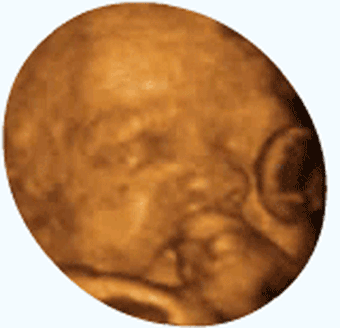

男孩和女孩的胎动有区别吗,为什么?

我认为男孩和女孩的胎动不会有太大区别,怀孕的时候自己是不会通过胎动来感觉到男孩还是女孩的。不同的孩子胎动会有区别,是因人而异,不是因性别而异。我生了两个男孩,这两个孩子胎动就大有不同,我朋友生的女孩,胎动也是有自己的规律。

我没有生过女孩子,但是从朋友的描述看,胎动并不像传说中的那样女孩懒动、男孩勤的。也不是男孩幅度大、女孩幅度小。我两个男孩就是一个懒一个勤、一个幅度大一个幅度小。所以,性别不同,胎动不一定有区别。